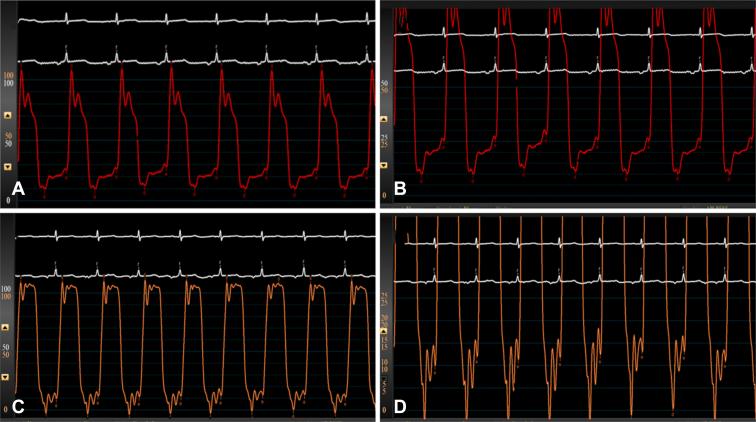

Diastolic dysfunction manifesting as acute plastic bronchitis after Warden procedure.

Pasternack Daniel M, Martinez Michael J, McKinstry Jacqueline, Singh Rakesh, Saharan Sunil, Muise Eleanor D, Mosca Ralph, Kumar T K Susheel

JTCVS Tech. 2024 Apr 3;25:153-156. doi: 10.1016/j.xjtc.2024.03.018. eCollection 2024 Jun.

Abstract

摘要